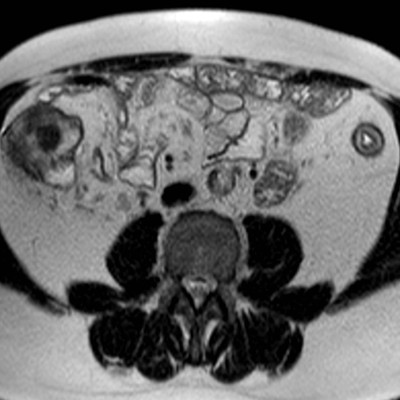

März 2017 von PD Dr. Peter Bannas aus Hamburg

Frage 1: Um welche Bildmodalität handelt es sich?

- a) MRT (native T2w-Sequenz sowie T1w-Sequenz mit Kontrastmittel)

- b) MRT (native T2w-Sequenz sowie native T1w-Sequenz)

- c) CT (portalvenöse und arterielle Phase)

- d) PET/CT (CT im Weichteilfenster und PET)

- e) CT (native und arterielle Phase)

Frage 2: Was führt in der benutzten Aufnahmetechnik am wenigsten wahrscheinlich zu Artefakten?

- a) Metallische Prothesen

- b) Luftansammlungen im Darm

- c) Bewegungen des Patienten während der Aufnahme

- d) Blutfluss

- e) Nierenzysten

Frage 3: Welche Struktur ist nicht erfasst?

- a) Colon descendens

- b) Colon ascendens

- c) Colon transversum

- d) Nieren

- e) Leber

Frage 4: Welcher Befund ist nicht vorhanden?

- a) Zielscheiben-Phänomen (Target-Sign)

- b) Ödem in der Submukosa

- c) Langstreckiger Verlust der Haustrierung

- d) Kontrastmittelanreicherung der Darmwand

- e) Pneumatosis intestinalis

Frage 5: Welche Diagnose stellen Sie?

- a) Colitis ulcerosa

- b) Colonkarzinom

- c) Lymphom

- d) Leiomyom

- e) Metastase

Preisfrage: Welche Erkrankung ist mit der Colitis Ulcerosa assoziiert?

- a) Primär biliäre Cholangitis

- b) Primär sklerosierende Cholangitis